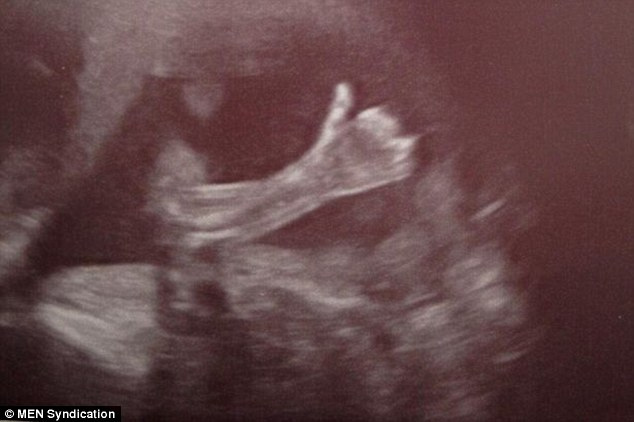

«¡Ey!, mamá y papá, por acá todo bien»: una ecografía de 20 semanas

El Daily Mail trae una de esas historias «tan suyas». Paul Schofield  y Cheryl Stevenson, matrimonio treintañero presenciaba la ecografía de las 20 semanas, la imagen de su segundo hijo. LSN también se hace eco.

La criatura les «regaló» un ok con el pulgar hacia arriba cuando era movida para poder determinar el sexo. Parecía decir, «no fastidien, por acá todo bien». Las enfermeras del Saint Mary de Manchester dijeron a la pareja, que estaba tronchada de risa, que nunca habían visto una imagen así.